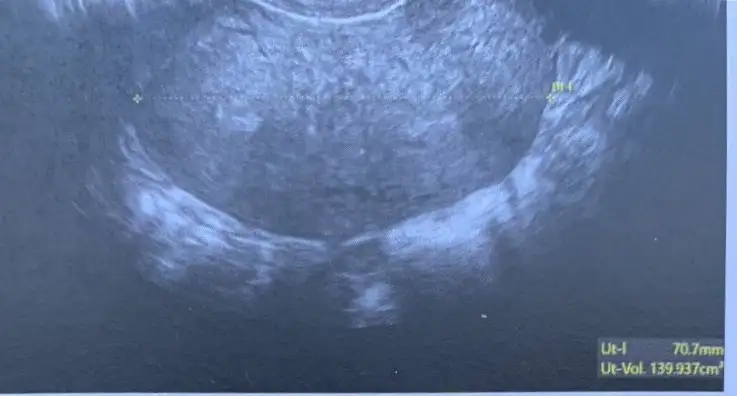

Amin canım Rabbim herkese hakkıyla annelik babalık nasip etsin inşallah. Bende önümüzdeki hafta Ankara’da Bülent zeyneloğlu nda rahim düzeltme ameliyatı olacağım. Benim hsg sonucu sağ tüpüm tıkalı sol hafif açık gibi çıktı ama Bülent hoca hsg nin çok kötü çekildiğini, histereskopi ile birlikte laparoskopi de yaparak tüplerin ne durumda olduğunu görmek istediğini söyledi. Eğer tüplerimde sorun varsa direk tüp bebeğe geçeceğiz zaten ama o süreci hiç yaşanmadan kendiliğinden olmasını çok istiyorum. Sen iki kere histereskopi olduğuna göre gayet kolay bir operasyon diye tahmin ediyorum ancak Bülent hoca benim için rahim çok aşırı y o yüzden tek operasyonla düzenlmeyebilir dedi. Umarım tek operasyonla hallolur tüplerimdede sorun yoktur hemen ertesi ay hamile kalırım. Hepsinin aynı anda olma ihtimali çok az ama Rabbim ol derse olur ne yapalım. Benim rahmim de bu şekilde bu arada

Amin canım Rabbim herkese hakkıyla annelik babalık nasip etsin inşallah. Bende önümüzdeki hafta Ankara’da Bülent zeyneloğlu nda rahim düzeltme ameliyatı olacağım. Benim hsg sonucu sağ tüpüm tıkalı sol hafif açık gibi çıktı ama Bülent hoca hsg nin çok kötü çekildiğini, histereskopi ile birlikte laparoskopi de yaparak tüplerin ne durumda olduğunu görmek istediğini söyledi. Eğer tüplerimde sorun varsa direk tüp bebeğe geçeceğiz zaten ama o süreci hiç yaşanmadan kendiliğinden olmasını çok istiyorum. Sen iki kere histereskopi olduğuna göre gayet kolay bir operasyon diye tahmin ediyorum ancak Bülent hoca benim için rahim çok aşırı y o yüzden tek operasyonla düzenlmeyebilir dedi. Umarım tek operasyonla hallolur tüplerimdede sorun yoktur hemen ertesi ay hamile kalırım. Hepsinin aynı anda olma ihtimali çok az ama Rabbim ol derse olur ne yapalım. Benim rahmim de bu şekilde bu arada.